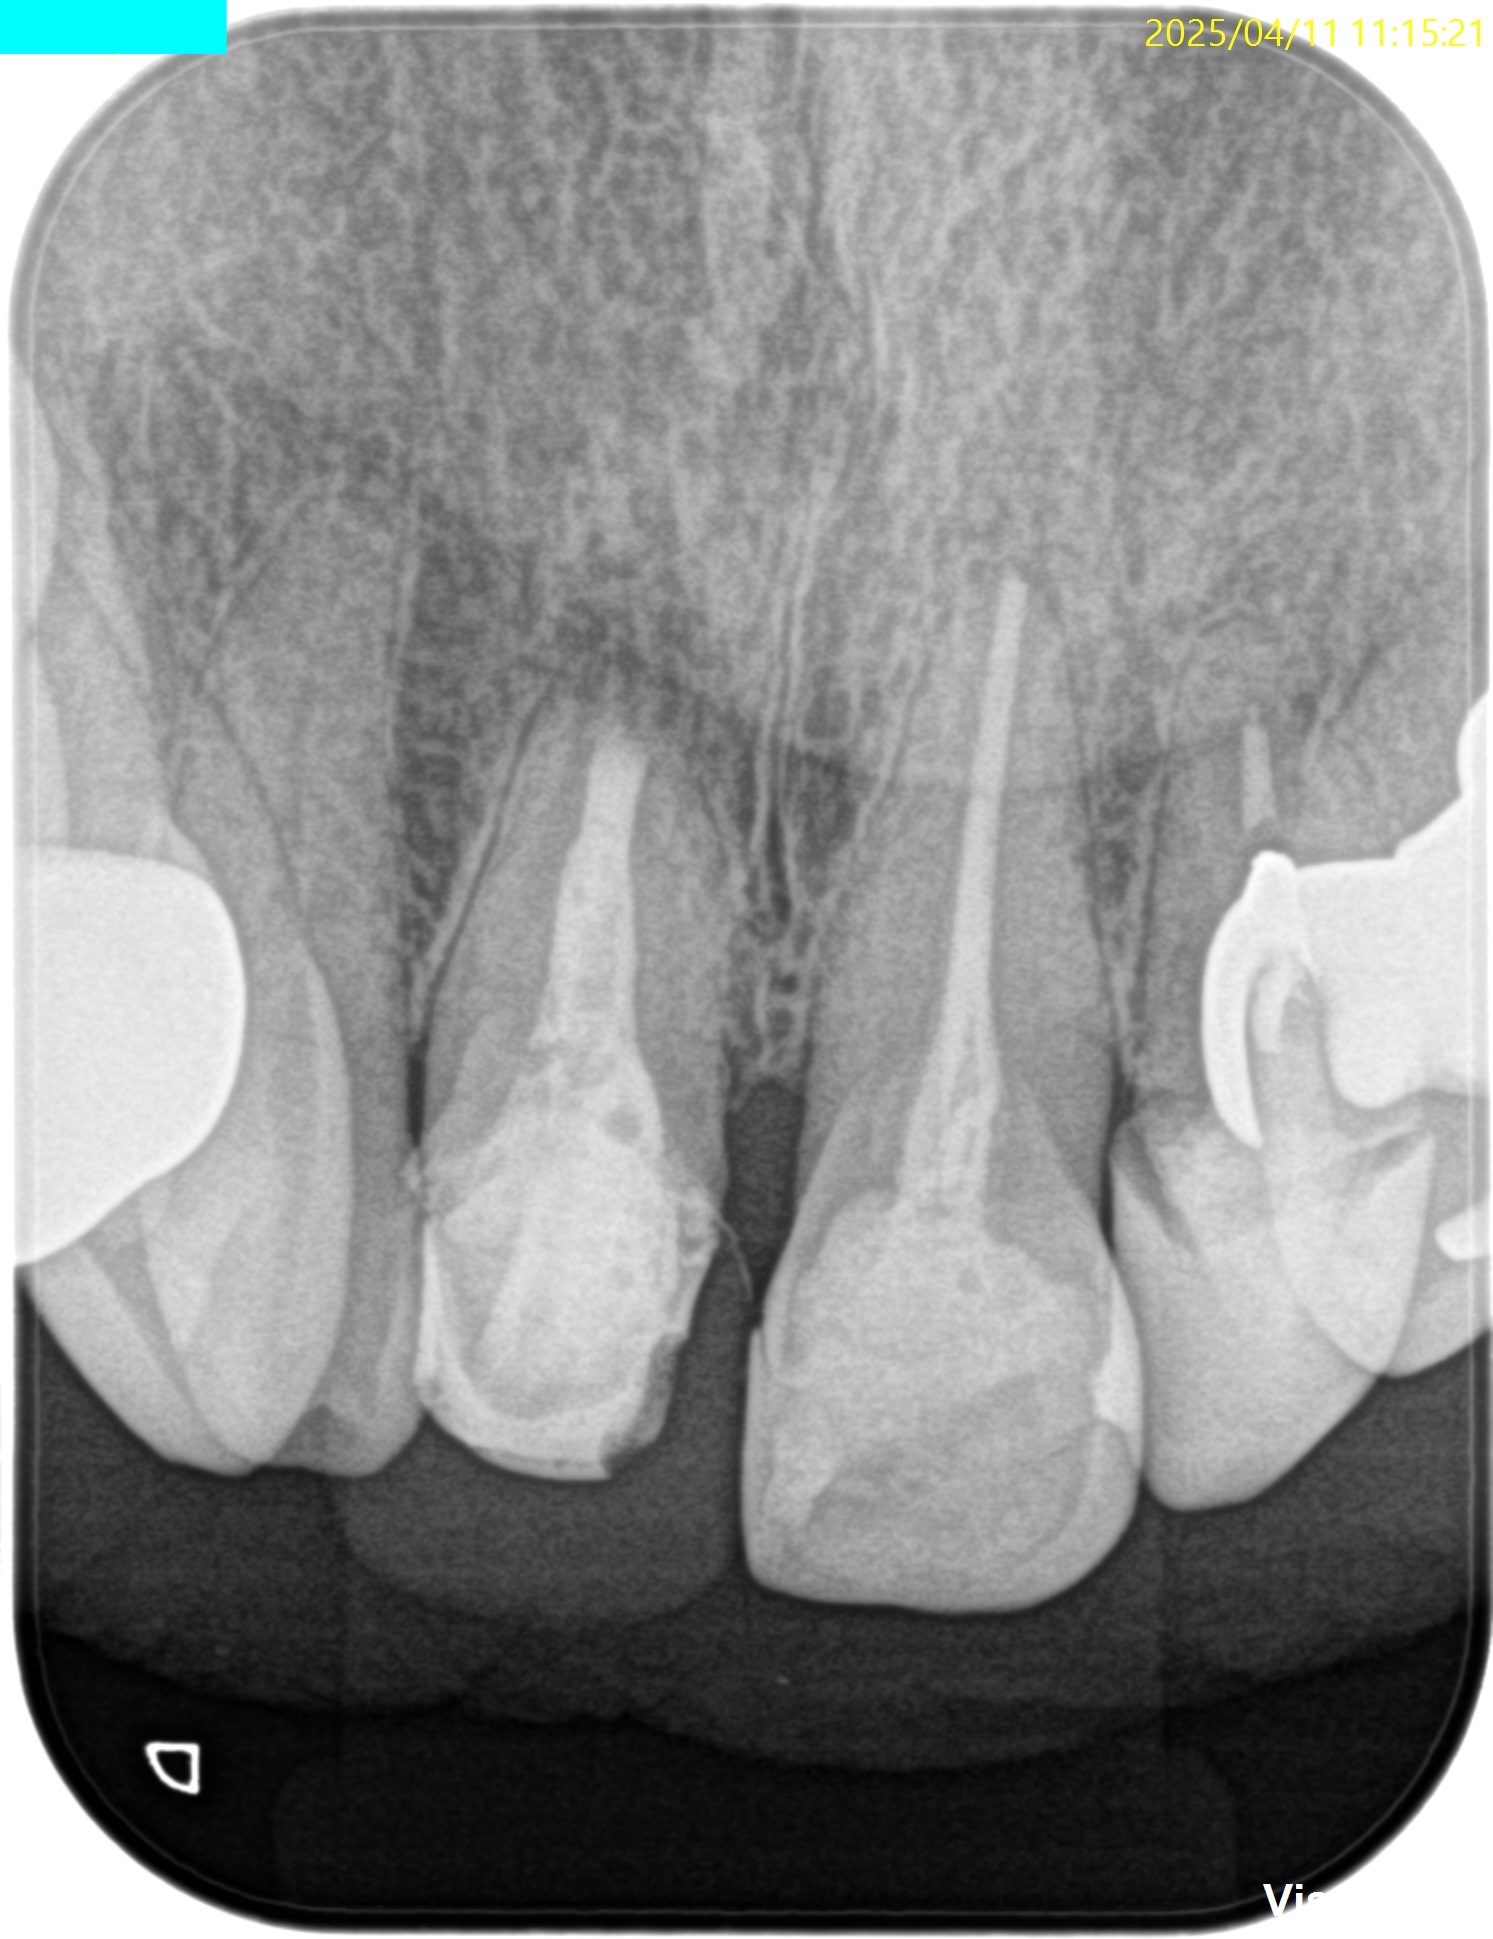

術後にPAを撮影した。

問題はないだろう。